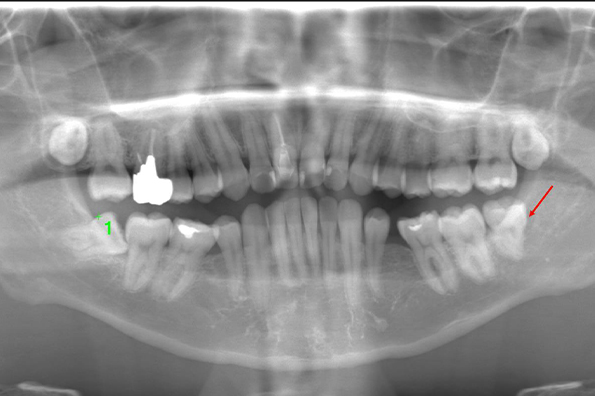

CASE 1

| 年齢・性別 | 30代・女性 |

|---|---|

| 主訴 | 左右に分けて親知らずを抜きたい、できれば痛くなく抜きたい |

| 親知らずのはえ方 | 完全に出ていてまっすぐはえている |

| 抜歯期間 | 15分 |

| 抜歯費用 | 約2,000円(保険内) |

| 抜歯内容 |

何度か虫歯になり痛みはないが早めに抜きたい。 完全に頭が出ているため歯ぐきを切ったり骨を削らずに抜歯しました。 根の形も単純なため抜歯自体は5分もかからず上下ともに終わりました。 術後痛みや腫れも出ていません。 抜歯後は感染をしやすいため必ず抗生物質を飲み切ってください。 |